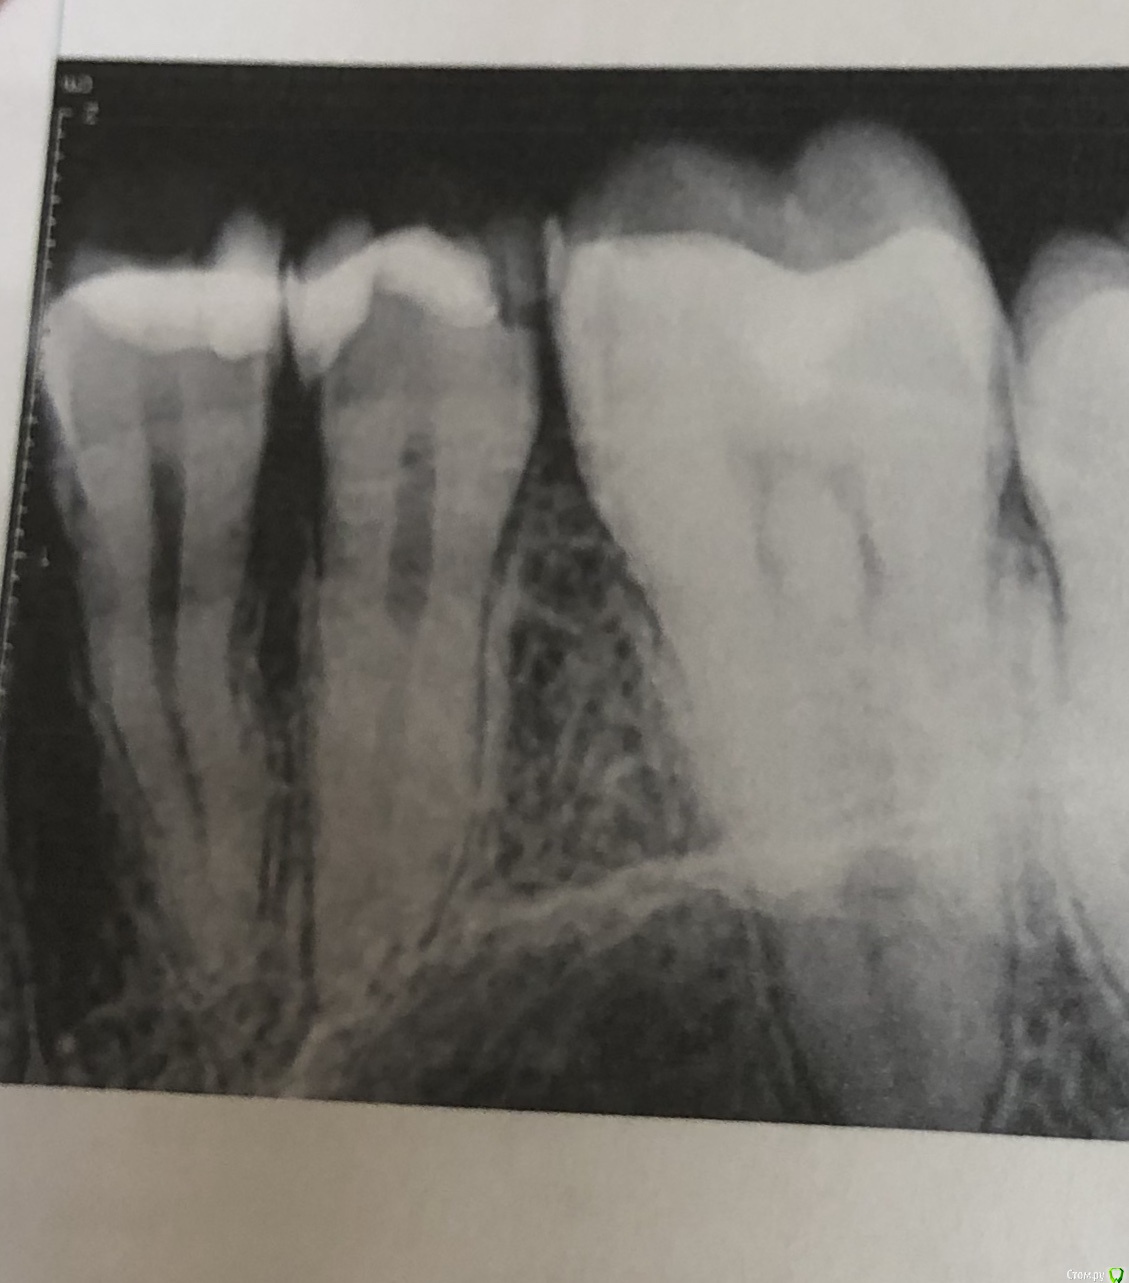

Olga2396 Опубликовано 6 октября, 2019 Поделиться Опубликовано 6 октября, 2019 (изменено) Зуб не болит 4й,но при постукивании чувствителен. Что с боку если постучат, что если постучать на жевательную поверхность.При первом лечении каналов зуб продолжал реагировать на горячее, был крайне чувствителен после горячего,языком было недотронуться. Врач перелечила каналы,боль уменьшилась,при надкусывании не больно, но непонятно почему если постучать неприятно, хотя с другими зубами у которых есть нерв нет неприятного ощущения. + переживаю из за того что выведено за верхушку корня, гуттаперча ли это? Или силлер, пломбировали мне кстати эндометазоном. Надо перелечивать? Или смотреть за состоянием зуба через пол года,будет ли увеличиваться чувствительность или уменьшаться.+ ко всему говорят об удаление нерва из 5го зуба. Зуб чувствителен на холодное,иногда горячее,но не пульсирует,ночных болей нет. Надо ли удалять? Говорят у меня анатомия зубов что нерв близко расположен к поверхности зуба,но при препарировании не была вскрыта пульповая камера и сказали дентин плотный, но 5 зуб чувствителен на холодное,но не больно,обезболивающее не пью и проходит сразу же. Я уже устала с этими зубами, вроде пролечила, а неприятных ощущения есть. 4й зуб пролечен уже как месяц. 5й пока не удаляют нерв смотря за динамикой,есть ли боли нет. Иногда сам как будто микротоком мимолетно стрельнет, ощущения как если бы укололи палец,не больно и пройдётсразу же. Не пульсирующая.1. До удаления нервов 4й5й зуб2. После удаления нерва,первая попытка (боли,чувствительностью горячее)3,4- после 2го лечения в разных боковых проэкциях снимок. Состояния на данный момент 4 и 5 зубаНа 5 снимке красным я отметила потемнее похоже на доп.ветвь канала. На снимках 3,4 есть это ответвление. Это доп. Канал?или особенность снимка? Изменено 6 октября, 2019 пользователем Olga2396 Ссылка на комментарий

red_butler Опубликовано 10 октября, 2019 Поделиться Опубликовано 10 октября, 2019 Четвертый пролечен достойно, дискомфорт при постукивании должен пройти. Зуб обязательно восстановите искусственной коронкой. Пятый, доктор оставил часть старой пломбы? По рентгену необходимости лечения каналов не увидел. По снимку есть вопросы по контактным пунктам между пятым и шестым - пломбировочный материал в межзубном промежутке, на шестом, его нужно убрать. Если боли в пятом быстро проходящие, и не исчезнут, то ставить вопрос о повторном лечении Ссылка на комментарий